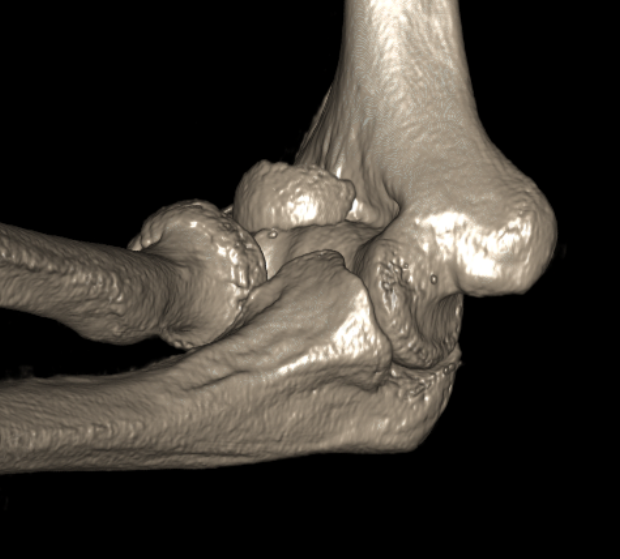

Knee

Approaches